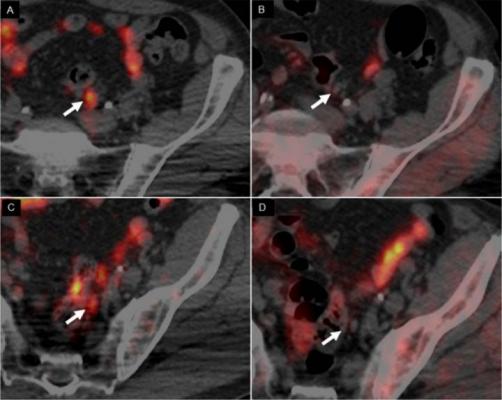

In scans of a 62-yr-old man with Gleason 4+3 PCa treated with radical prostatectomy, with rising PSA level (1.32) and PSA doubling time of 3.7 months, 64CuCl2-PET/CT images revealed 2 positive small left iliac lymph nodes (A,C), whereas 18F-Choline PET/CT (B,D) was negative (arrows). Image courtesy of A Piccardo et al., Galliera Hospital, Genoa, Italy.

Copper tends to be more concentrated in tumors, making it a good imaging biomarker. For this study of 50 patients, researchers conducted PET/CT scans comparing the new imaging agent, copper-64 chloride (64CuCl2), with fluorine-18-choline (18F-Choline). Multiparametric magnetic resonance imaging (mpMRI) was also conducted. In addition to calculating the detection rate of each imaging modality, the biodistribution, kinetics of the lesions and radiation dosimetry of 64CuCl2 were evaluated.

The effective dose of 64CuCl2 was determined to be 5.7 mSv, similar to those of other established PET tracers (although higher than for 18F-Choline, which is 4 mSv). Unlike 18F-Choline, 64CuCl2 is neither accumulated in, nor excreted from, the urinary tract (main uptake is in the liver); this allows for thorough pelvic assessment, increasing the possibility of identifying small lesions close to the bladder. No adverse reactions were observed after the injection of 64CuCl2, and results show that 64CuCl2-PET/CT has a higher detection rate than 18F-Choline-PET/CT in patients with low levels of PSA (<1 ng/ml).

"This study determined that the biodistribution of 64CuCl2 is more suitable than that of 18F-Choline for exploring the pelvis and prostatic bed," said Piccardo. "In patients with biochemical relapse and a low PSA level, 64CuCl2-PET/CT shows a significantly higher detection rate than 18F-Choline-PET/CT." He reports, "Larger trials with this PET tracer are expected to further define its capabilities and role in the management of prostate cancer."